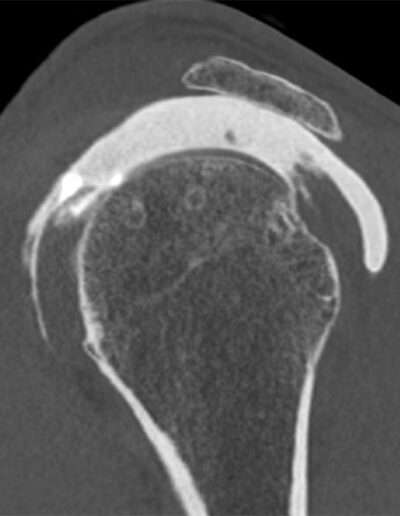

Shoulder Left

Patient 45 y/o, Male, right-handed

• 2003: Open surgery for AC joint dislocation (Dr. Elsewhere)

• 10/2024: Rotator cuff repair (Dr. Thibault LAFOSSE)

• Pain and instability 3 months postoperative, triggered by carrying a bag